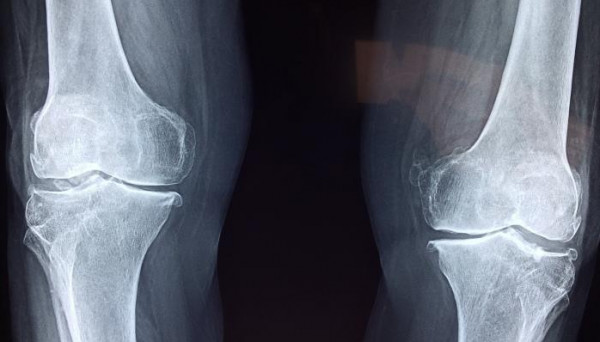

طريقة لإعادة نمو الغضروف.. تعرف عليها

تعتبر عمليات زرع غرسات كهربائية هو العلاج والحل الأمثل لملايين مرضى التهاب المفاصل حيث تمكن العلماء من إعادة نمو الغضروف بمساعدة التيارات الكهربائية.

وفقًا للدراسة، التي نُشرت في العدد الجديد من دورية Science Translational Medicine، يمكن أن تؤدي حركة المفصل المنتظمة إلى قيام الغرسة بتوليد مجال كهربائي في ركبة مريض التهاب المفاصل مما يحفز الخلايا على النمو حولها وتكوين غضروف جديد.

إن مرض التهاب المفاصل شائع ومؤلِم وينتج عن تلف مفاصل المريض، وعلى الرغم من أن حشوات الغضاريف عادة ما تخفف الألم في تلك النقاط، إلا أن الإصابات أو التقدم في السن يمكن أن يتسبب في تآكلها.

مع تدهور حالة الغضروف، تبدأ العظام في الاصطدام ببعضها البعض، وبالتالي يعاني المريض من ألم رهيب عند ممارسة الأنشطة اليومية مثل المشي، لذا فإن نمو الغضروف الجديد هو المفتاح لجعل الحالة أقل إيلامًا.